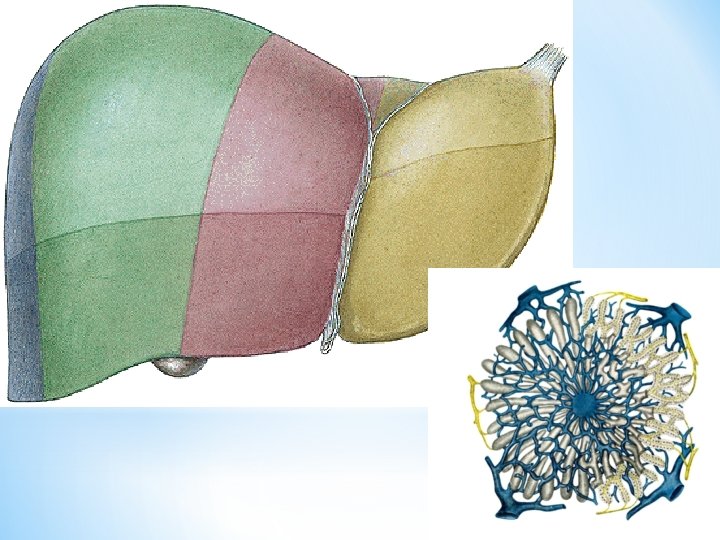

HEPAR Facies diaphragmatica pars superior area nuda pars

HEPAR

Facies diaphragmatica - pars superior (area nuda) - pars anterior - lig. falciforme hepatis - lobus dexter - lobus sinister Facies visceralis Fissura ligamenti teretis (lig. teres hepatis) Fissura ligamenti venosi

Fossa vesicae biliaris Sulcus venae cavae Lobus dexter sinister caudatus quadratus Porta hepatis - vena portae - a. hepatica propria - ductus hepaticus communis (portal triad)